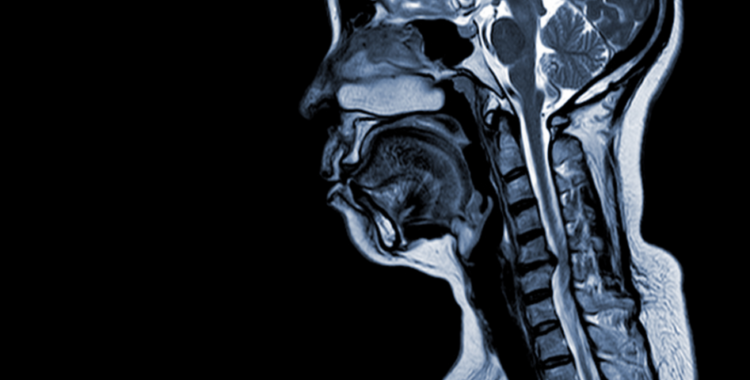

Ce este esențial de înțeles e că mielopatia nu este o simplă durere de spate. Este rezultatul unei presiuni constante asupra măduvei spinării, care, în timp, poate duce la deteriorări dificil sau imposibil de reversat. Dacă ai primit acest diagnostic sau ai suspiciuni, nu ezita să mergi la un specialist în neurochirurgie. Un RMN poate arăta clar sursa compresiei și gravitatea leziunii.

Gândește-te la măduva spinării ca la un „cablu” principal care transmite toate comenzile și informațiile dintre creier și restul corpului. Compresia prelungită a acestui cablu, așa cum se întâmplă în cazul unei hernii de disc, poate afecta mersul, coordonarea mâinilor, reflexele, forța musculară și chiar funcțiile esențiale de zi cu zi.